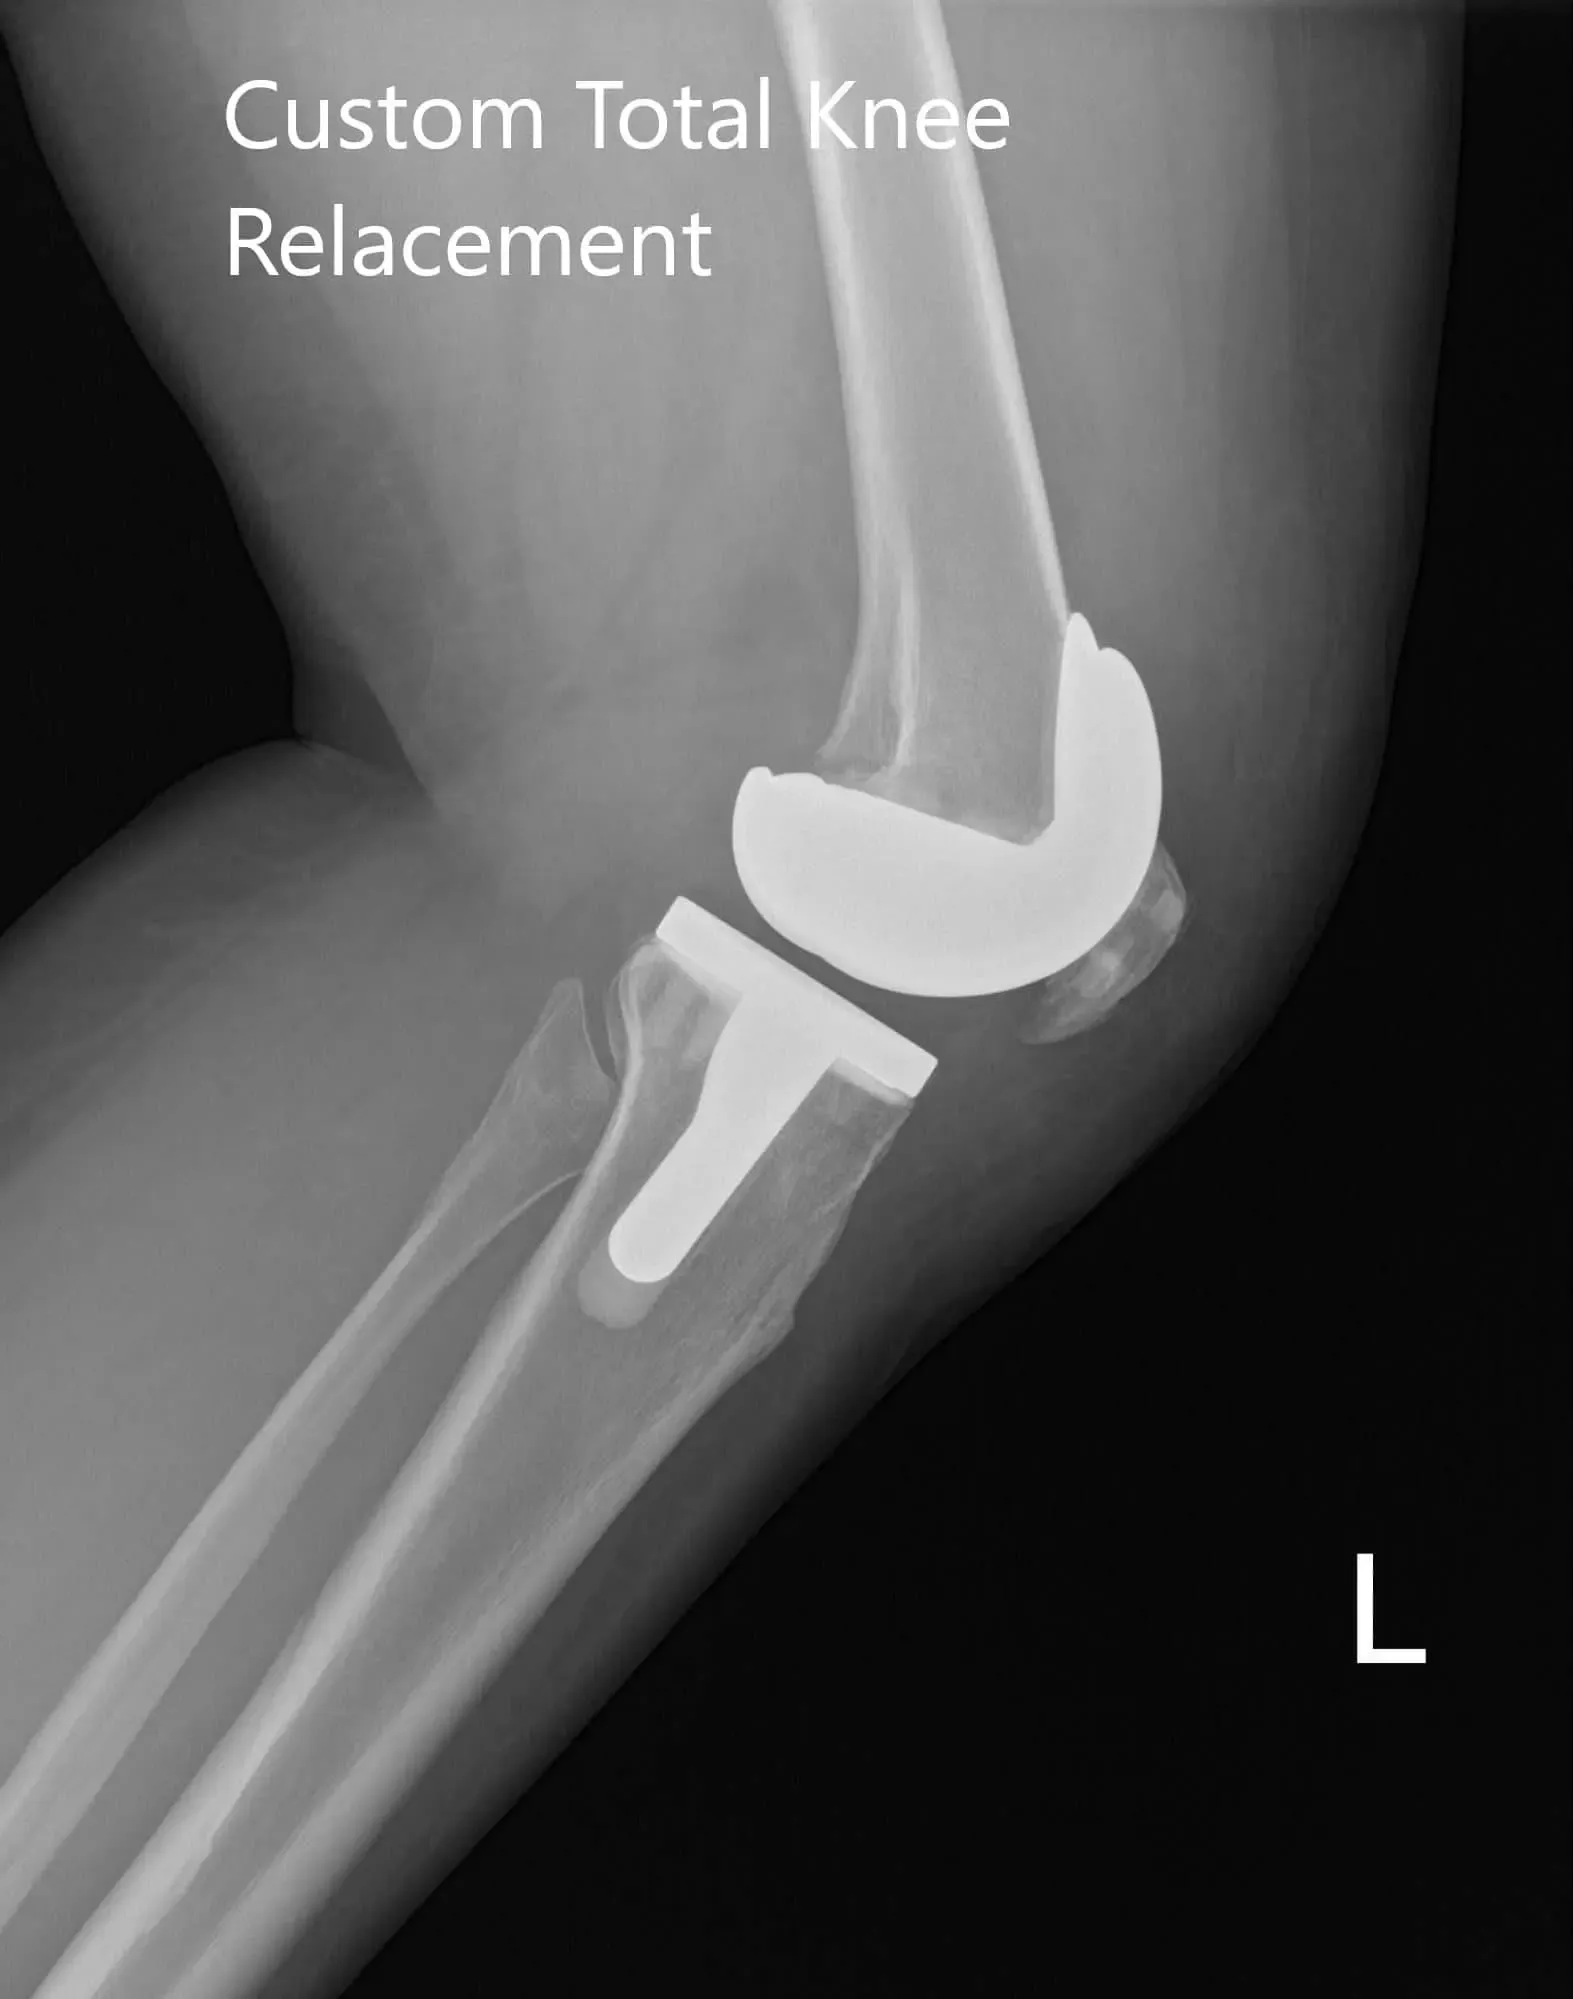

Radiografía postoperatoria de la rodilla izquierda que muestra imágenes AP y laterales

El paciente fue ambulatorio el mismo día de la cirugía. Informó de un buen control del dolor con medicación y un buen rango de movimiento alrededor de la rodilla izquierda. La herida del paciente estaba limpia, seca e intacta. Tenía una excelente adherencia a la fisioterapia y al programa de ejercicio en casa. No mostró dolor (0/10) y un excelente rango de movimiento tras 3 meses.

El paciente había terminado con éxito su fisioterapia y volvió a trabajar como profesor. Le encanta la libertad de movimiento jugando entre niños. Pudo volver a hacer senderismo moderado y montar en bicicleta sin dolor. La pareja se alegró diciendo que los resultados habían superado sus expectativas. Él responde cuando es necesario.